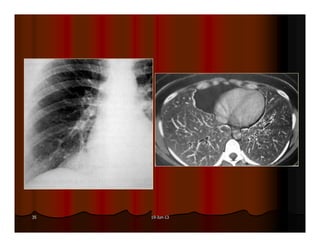

ASPERGILLOME

77 June 19, 2013

DẤU HIỆU LỤC LẠC

(SIGN OF TINTINNABULUM)

Sign of tintinnabulum = Signe de grelot.

Nấm Aspergillus có thể gây bệnh ở người với 2 thể chính:

Thể xâm lấn mạch máu (Angioinvasive Aspergillosis): tổn

thương lan toả, gặp ở người có cơ địa suy giảm miễn dịch. Ở

thể này ta có dấu hiệu vầng hào quang (halo sign) trên CT.

Thể banh nấm (Saprophytic Aspergillosis = Aspergilloma):

hình thành banh nấm (fungus ball) trong lòng các tổn thương

hang ở phổi, thường gặp ở BN có hang lao. Thể này cho dấu

hiệu lục lạc (Tintinnabulum sign) hay dấu hiệu liềm khí (Air

crescent sign) tuỳ theo tác giả.